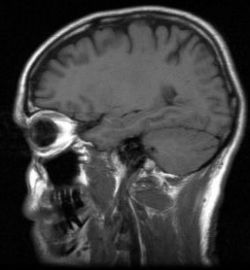

Mozog je výzvou pre celú vedu

Odhalenie fungovania mozgu je jedným zo základných problémov prírodnej vedy. Pochopenie funkcie takého zložitého systému, ktorý je dokonca schopný uvedomovať si sám seba, svoju vlastnú existenciu, je obrovskou záhadou a výzvou pre celú vedu

Mozog človeka je ústredný orgán nervovej sústavy a tvorí zložité zoskupenie vyšších a najvyšších nervových centier